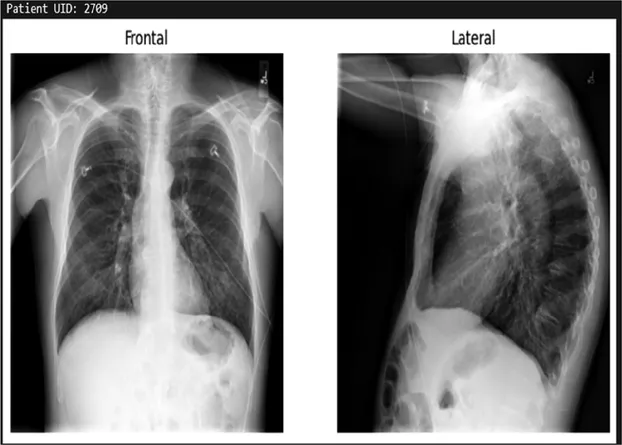

Training details

The dataset used in this study is the Indiana University Chest x-ray Dataset, which consists of 7,430 images of frontal and lateral chest x-rays belonging to 3,825 patients. Each image is paired with corresponding radiology reports that provide detailed findings regarding the patients' conditions. This dataset serves as the foundation for training the model to generate textual descriptions based on visual inputs.

Table 3. Example predictions of ChestX-transcribe.